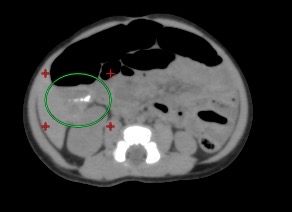

• 肝内の濃度はやや不均一で、ところどころ低吸収に見える部分がある。絶対的な CT 値は40~50 でそれほど低くなく、また血管内ガスも存在し、可視的でない部分でも肝内の CT 値を下げている可能性があるため断言できないが、脂肪浸潤を見ている可能性がある。 成人の死後 CT では前記のような所見を時々経験するものの、小児の死後 CT では個人的経験に過ぎないがミトコンドリア呼吸鎖異常の micro-vesicular fatty infiltration はこの様に見えたことがあり、SIDS の鑑別として当然考慮される疾患であるが、異常所見の可能性を記しておく。

• 肝内のガスは肝静脈内のものであり、蘇生時の右心系からの逆流により流入したものではないかと推測する。

• 肝内の濃度の不均一化。明確な異常とできるかどうかわからないが、読影者のうち 1 名 は、本文で記したようにミトコンドリア呼吸鎖異常の micro-vesicular fatty lover がこの 様に見えた経験があると述べていたのを参考に附す。